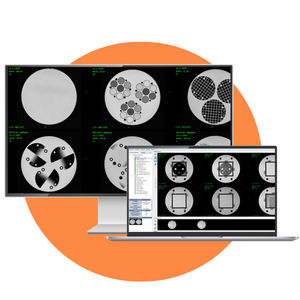

... Para satisfacer las necesidades de control de calidad de los generadores de imágenes de IRM, ofrecemos el MR QA Pack. Para este paquete, seguimos las siguientes recomendaciones: Programa de acreditación de RM del ACR Principales parámetros ...

AQUILAB